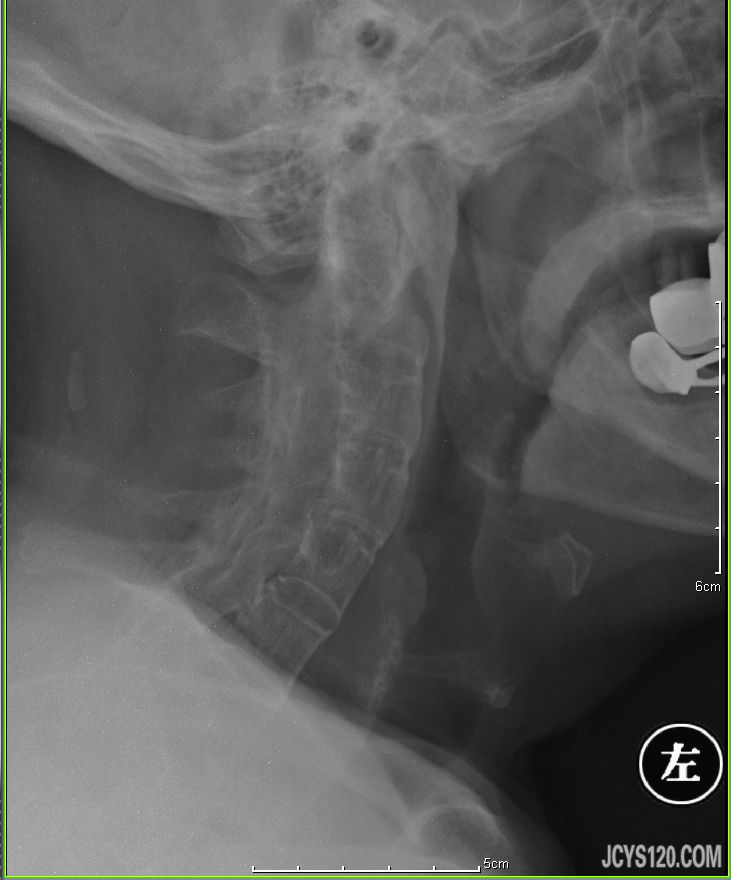

同行帮给看一下这个造影,需要怎么治疗比较理想